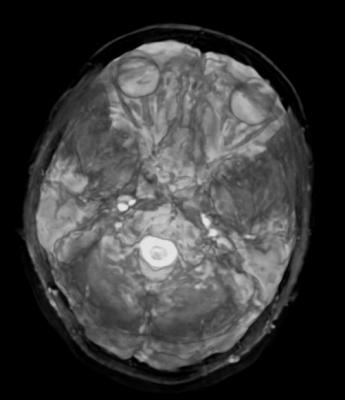

The new pathology modules provide an overview of how MR can identify pathological conditions and its ability to evaluate traumatic injuries. The modules describe the pathology of the vascular system of the neck and head, brain, spine, abdomen, and pelvis and extremities. The new modules incorporate 110 images depicting 49 pathologies.